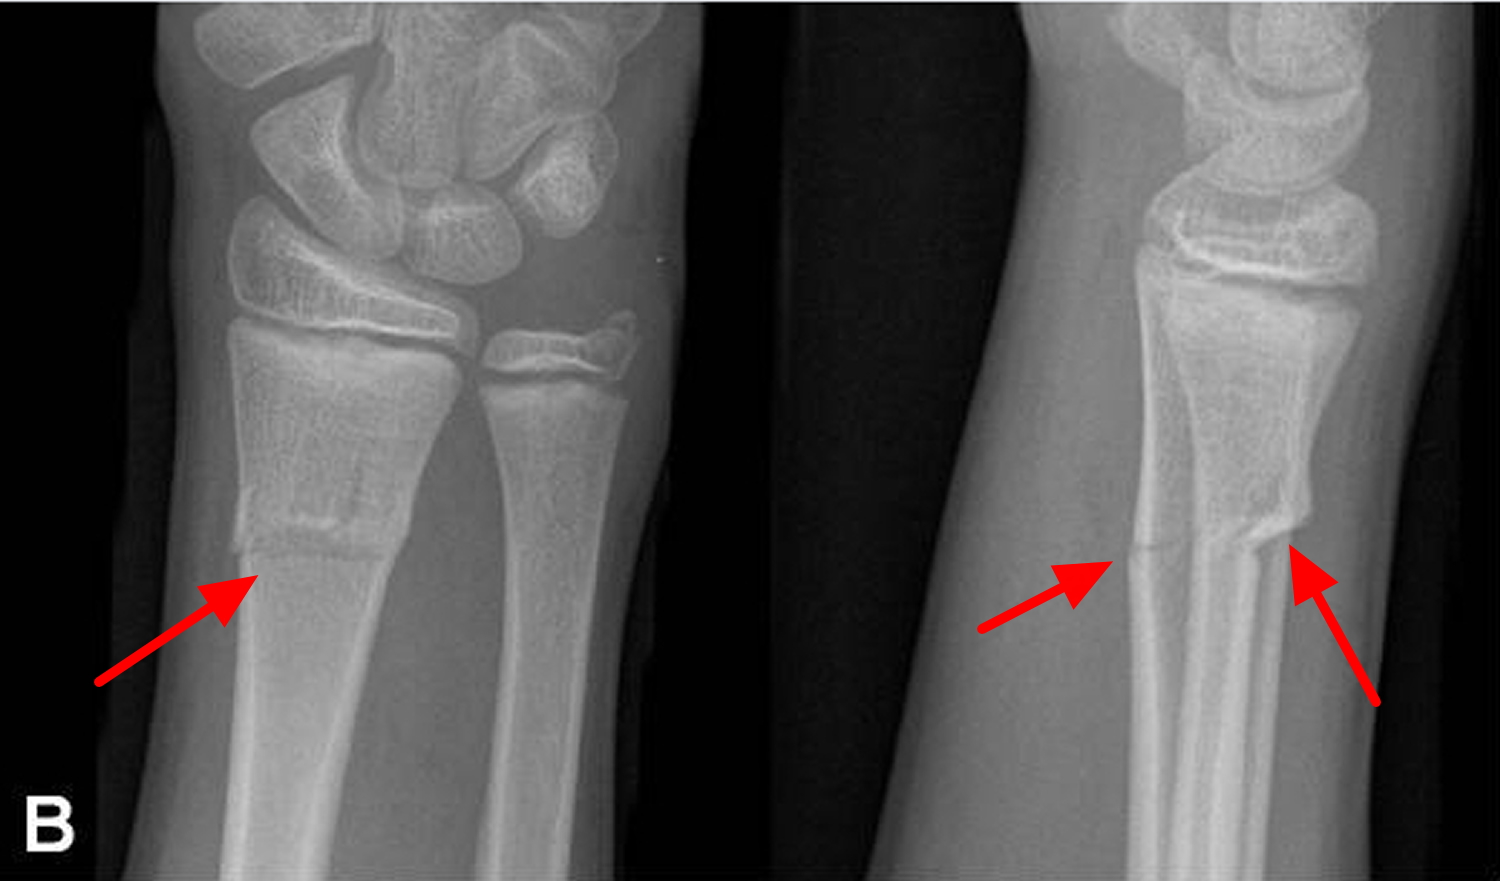

골막이 두껍고 뼈가 유연하기 때문에 뼈가 한쪽 만 부러지는 경우가 생기는데 패이는 형태의 green stick fracture 나 한쪽 피질 골이 접히는 것처럼 보이는 Torus fracture 등의 형태로 성인에서 볼 수 없는 골절 양상이 생길 수 있습니다. 또한, 가소성이 매우 높기 때문에 Wolf's law 등을 고려해 보았을 때 어느정도 근육과 해부학적인 힘의 매커니즘 형태로 (주로 이전의 모습) 복구하려는 모습을 보일 수 있습니다. 골절의 변형 규모가 매우 커도 단순한 석고고정 치료만으로도 치료가 가능한 이유입니다. 물론, 이러한 치료 판단 기준은 반드시 정형외과 전문의를 통해 이루어져야 합니다.